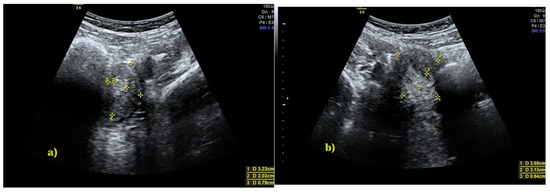

Background and Clinical Significance: Herlyn–Werner–Wunderlich (HWW) syndrome, also known as OHVIRA syndrome (Obstructed HemiVagina and Ipsilateral Renal Anomaly), is a rare congenital anomaly of the female urogenital system characterized by uterine duplication, unilateral vaginal obstruction, and renal agenesis on the same side. [...] Read more.

Background and Clinical Significance: Herlyn–Werner–Wunderlich (HWW) syndrome, also known as OHVIRA syndrome (Obstructed HemiVagina and Ipsilateral Renal Anomaly), is a rare congenital anomaly of the female urogenital system characterized by uterine duplication, unilateral vaginal obstruction, and renal agenesis on the same side. The condition often remains undiagnosed until adolescence, when it presents with palpable pelvic mass, dysmenorrhea, and chronic pelvic pain. Case report: We present the case of a 13-year-old female patient diagnosed with OHVIRA syndrome following imaging studies. Surgical treatment involved incision of the vaginal septum and evacuation of accumulated blood, leading to symptom resolution and restoration of reproductive tract patency. Conclusions: This article discusses the clinical characteristics, diagnostic challenges, and the importance of early surgical intervention, emphasizing the necessity of considering this syndrome in the differential diagnosis of adolescent females with cyclic abdominal pain and renal anomalies. Early diagnosis and treatment can prevent severe health complications and improve both patients’ quality of life and fertility. Full article

Figure 1